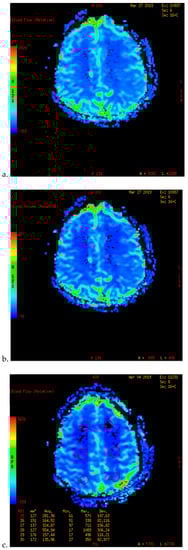

Figure 1.

PWI of patients with TND in the perioperative period after operation (example 1). (a) The PWI image on the day before operation showed that the cerebral blood flow (CBF) of both sides was basically the same. (b) On the 7th day after right combined revascularization, the patient developed epileptic symptoms. PWI examination showed that the CBF in the right operating area was significantly higher than that in the contralateral side on the 13th day after operation. (c) The patient’s TND symptoms recovered after more than ten days of repeated attacks. Two months after discharge, PWI showed that the cerebral blood flow of the two hemispheres tended to balance.